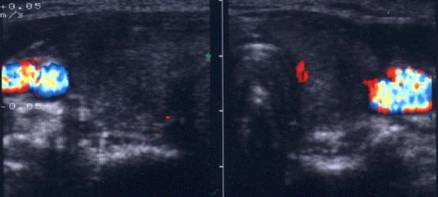

Aceeasi pacienta. La ecodoppler color - vascularizatie

periferica, avascular intralezional.

Ecopowerdoppler confirma absenta vascularizatiei interne.